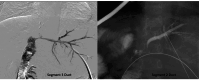

Figure 12

Figure 12. TIPS procedure

(a) Shunt track was created across the right hepatic vein and right branch of the portal vein using the Rösch-Uchida set (Cook Medical, Bloomington, USA). (b) The parenchymal tract was dilated, and a 10 mm x 10 cm stent (Niti-S, Taewoong Medical, Gimpo-si, South Korea) was successfully placed. (c) Post-stenting portogram showing good flow through the shunt. TIPS: Transjugular intrahepatic portosystemic shunt